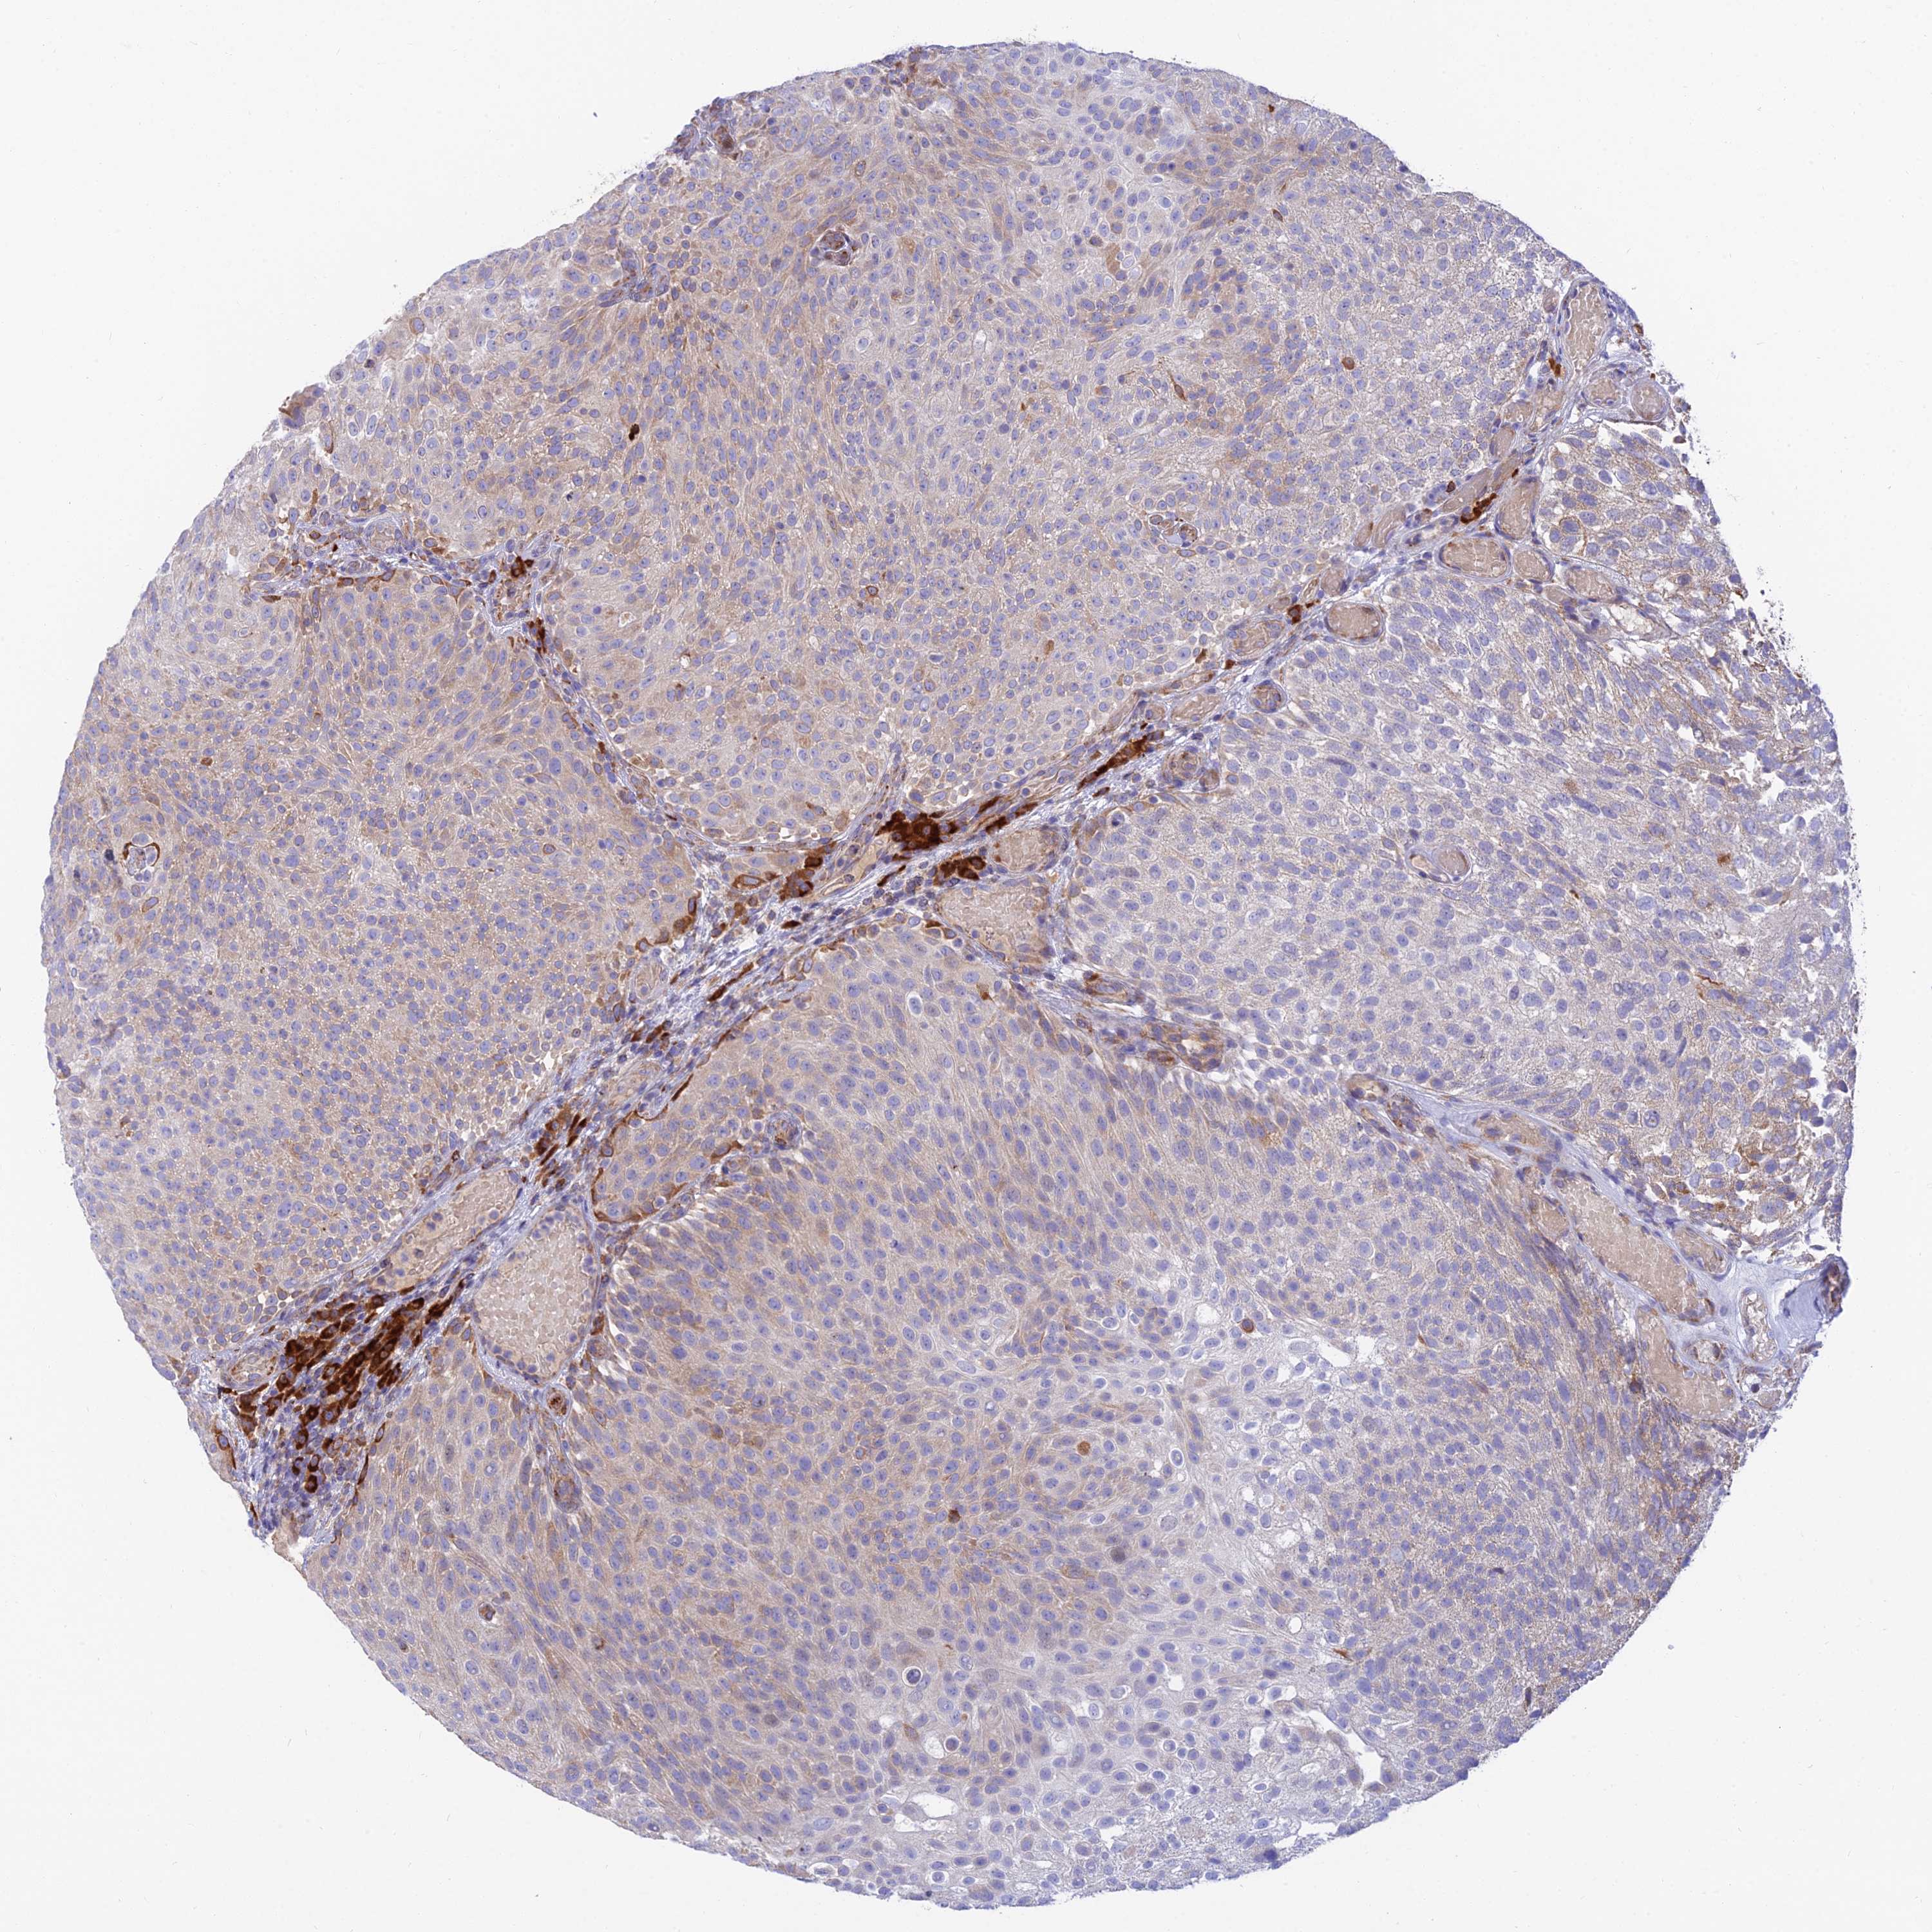

UROTHELIAL CANCER - Protein expressioni

A mouse-over function shows sample information and annotation data. Click on an image to view it in a full screen mode. Samples can be filtered based on level of antibody staining by selecting one or several of the following categories: high, medium, low and not detected. The assay and annotation is described here.

Note that samples used for immunohistochemistry by the Human Protein Atlas do not correspond to samples in the TCGA dataset.

Antibody stainingi

Antibody staining in the annotated cell types in the current human tissue is reported as not detected, low, medium, or high, based on conventional immunohistochemistry profiling in selected tissues. This score is based on the combination of the staining intensity and fraction of stained cells.

Each image is clickable and will lead to virtual microscopy that enables deeper exploration of all samples and also displays staining intensity scores, fraction scores and subcellular localization as well as patient and tissue information for each sample.

Antibody HPA042981

Staining

High

Medium

Low

Not detected

Intensity

Strong

Moderate

Weak

Negative

Quantity

>75%

75%-25%

<25%

None

Location

Nuclear

Cytoplasmic/membranous

Cytoplasmic/membranous,nuclear

Urothelial carcinoma, High grade

Urothelial carcinoma, Low grade